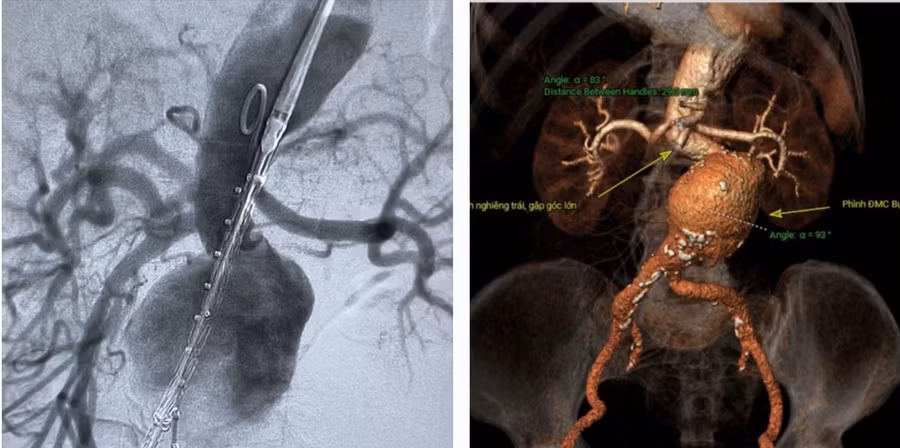

![]() |

| Hình ảnh sau khi can thiệp, túi phình lớn động mạch chủ bụng đã trở lại bình thường. |